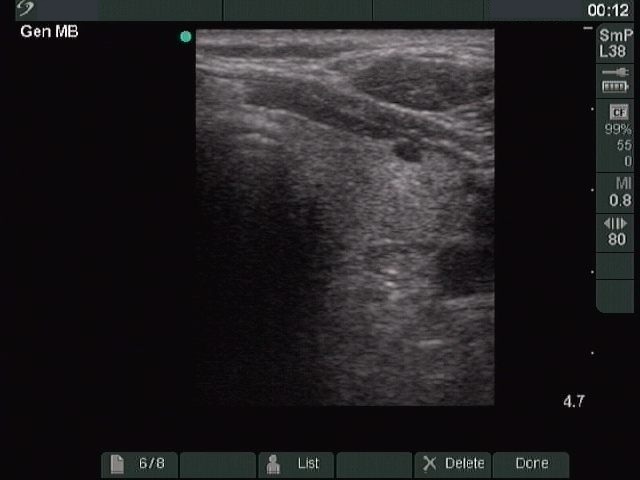

Ultrasonography: a hypoechogenic nodule with dimensions 29x24x33 mm. The nodule presented neither halo sign, nor perinodular blood flow.